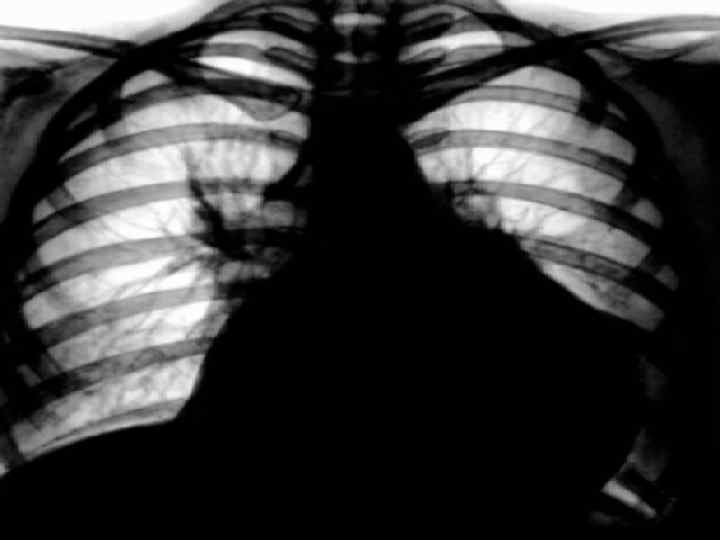

Инструментальные данные тампонады сердца: • ЭКГ – признаки: уменьшение амплитуды зубцов, высокие остроконечные зубцы Т в грудных отведениях либо картина, свойственная выпотным перикардитам • ЭХОКС: накопление жидкости в перикарде, наличие диастолического коллапса правого предсердия и правого желудочка; наличие дилатации нижней полой вены; • Рентгеновское исследование грудной клетки: cor «бутылка воды» , увеличение размеров сердца, сглаженность сердечных дуг, уменьшение амплитуды пульсации или полное ее исчезновение. • КТ сердца для выявления поражения перикарда

Диагностика хронических перикардитов • ЭКГ – подъем ST до 3 мес без формирования патологического Q; снижение вольтажа QRS • ЭХОКС – наличие жидкости в перикарде более 1, 0 см до 4, 0 см • R – графия легких ( конусообразная тень сердца), кальцинаты перикарда • Биохимия – показатели печеночной недостаточности

Рентгенологическое исследование • При хроническом течении экссудативного перикардита: наличие участков обызвествления в области перикардиальной тени и резкой очерченности линии ее контура. • Границы сердечной тени приобретают треугольную форму в отличие от шаровидной при остром выпотном перикардите.

Рентгенологическое исследование • На р-грамме обычно хорошо видны спайки перикарда с плеврой и диафрагмой. • Контур сердца приобретает зубчатый характер. Сращение сердца с диафрагмой образует лентообразную тень, сердце опущено и тесно прилежит к диафрагме. • При дыхательных экскурсиях сердце оказывается фиксированным и не меняет конфигурации.